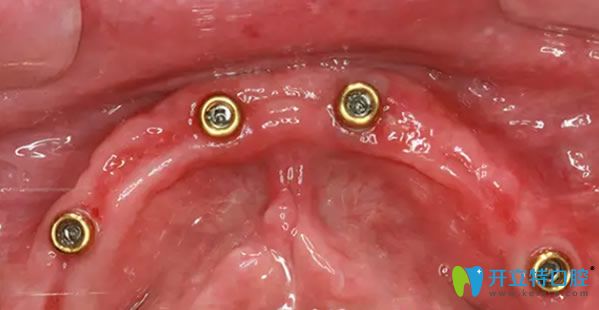

到院后,譚院長通過CT進(jìn)行數(shù)據(jù)采集,電腦精密計算人工牙根的植入位置,精準(zhǔn)制定種植方案,先把種植體種在牙槽骨內(nèi),然后再等恢復(fù)。外婆年紀(jì)大了,父母總擔(dān)心,種植過程中疼痛怕她承受不了。譚院長說我們的擔(dān)心都是多余的,會緊張那是必然的,手術(shù)是通過高氧恢復(fù),能夠讓高齡老人種牙后得到更好的調(diào)養(yǎng),真正實(shí)現(xiàn)無痛種牙。

種植前CT效果: